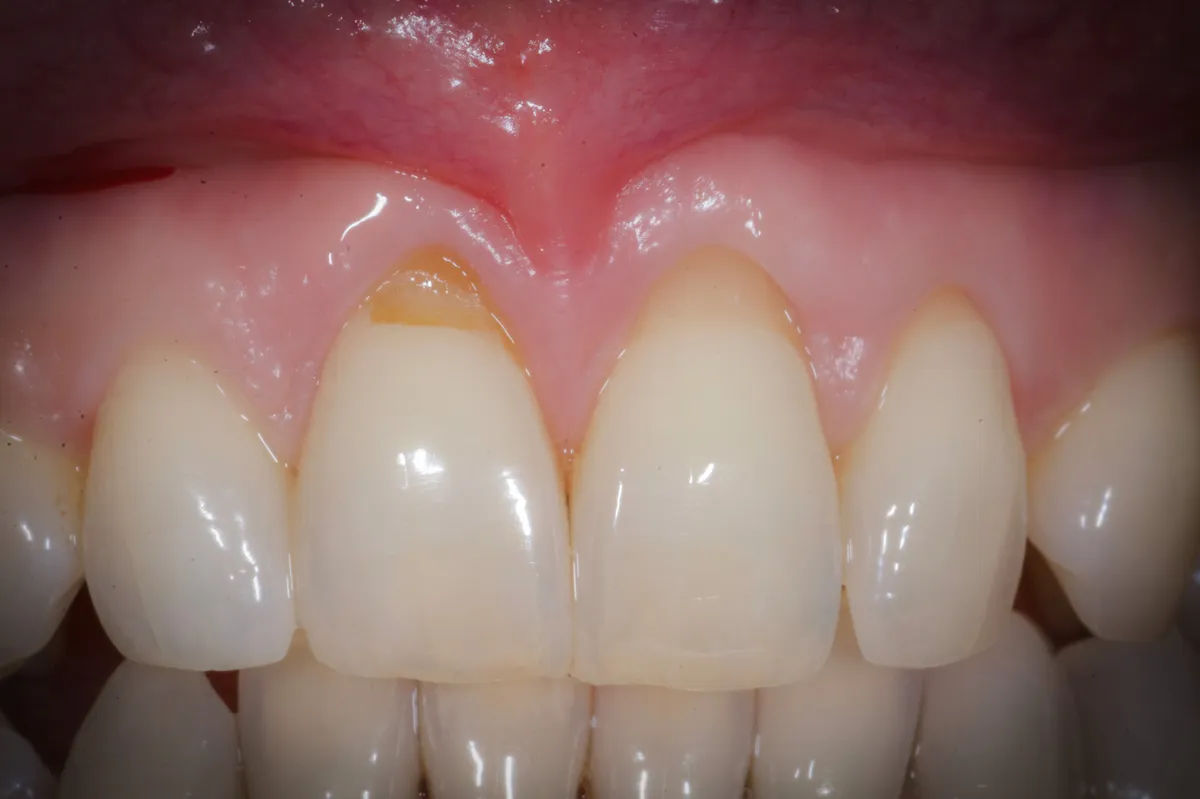

Caso clinico: espansione crestale ERE con impianto immediato e rigenerazione simultanea. Da ponte fallito a impianto in un'unica seduta.

Testimonianza reale di impianti dentali a carico immediato dopo trauma sportivo. Dopo 17 anni, risultati perfetti. Scopri come tornare a sorridere subito.

Bonebenders: espansione osteo-mucosa naturale per impianti. 100% osso e mucosa cheratinizzata senza biomateriali. Caso clinico e risultati straordinari.